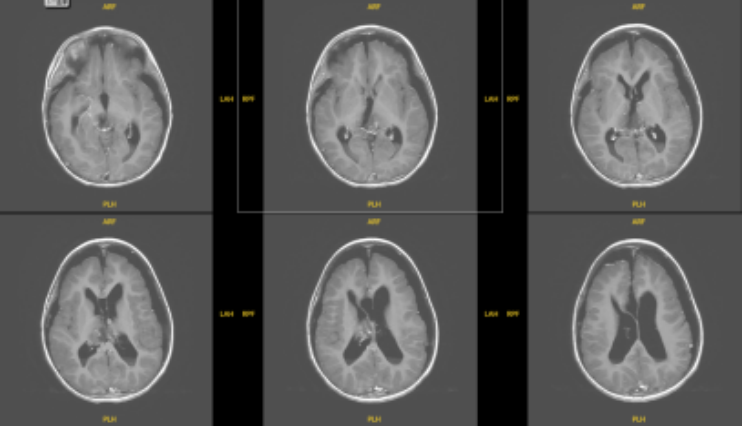

患儿术后MRI图像

术后病理考虑为颅内间叶源性肿瘤,非脑膜上皮来源。FISH提示EWSR1不典型断裂阳性。术后MRI显示肿瘤完全切除。目前患儿情况稳定,由ICU转入普通病房。

患儿术后MR影像:松果体区肿瘤组织切除完全